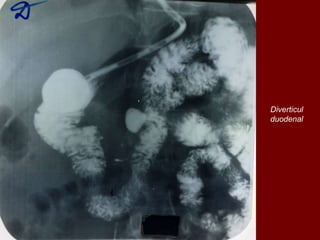

Diverticul

duodenal

Localizare:

• 90% bulb

• 10% postbulbar